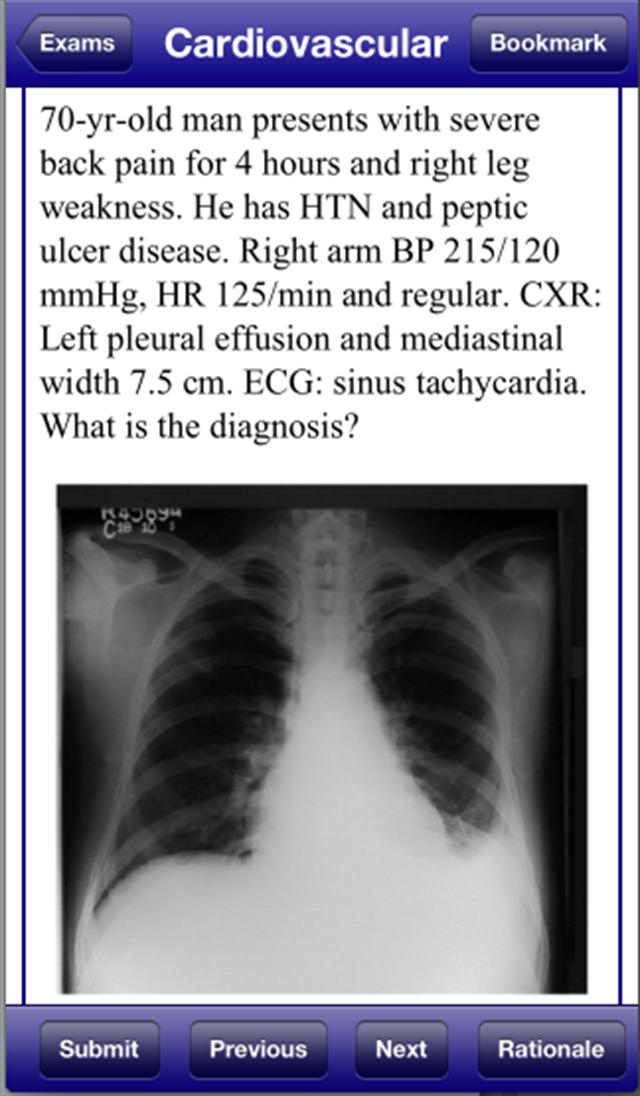

USMLE 2 Stanford Review Course